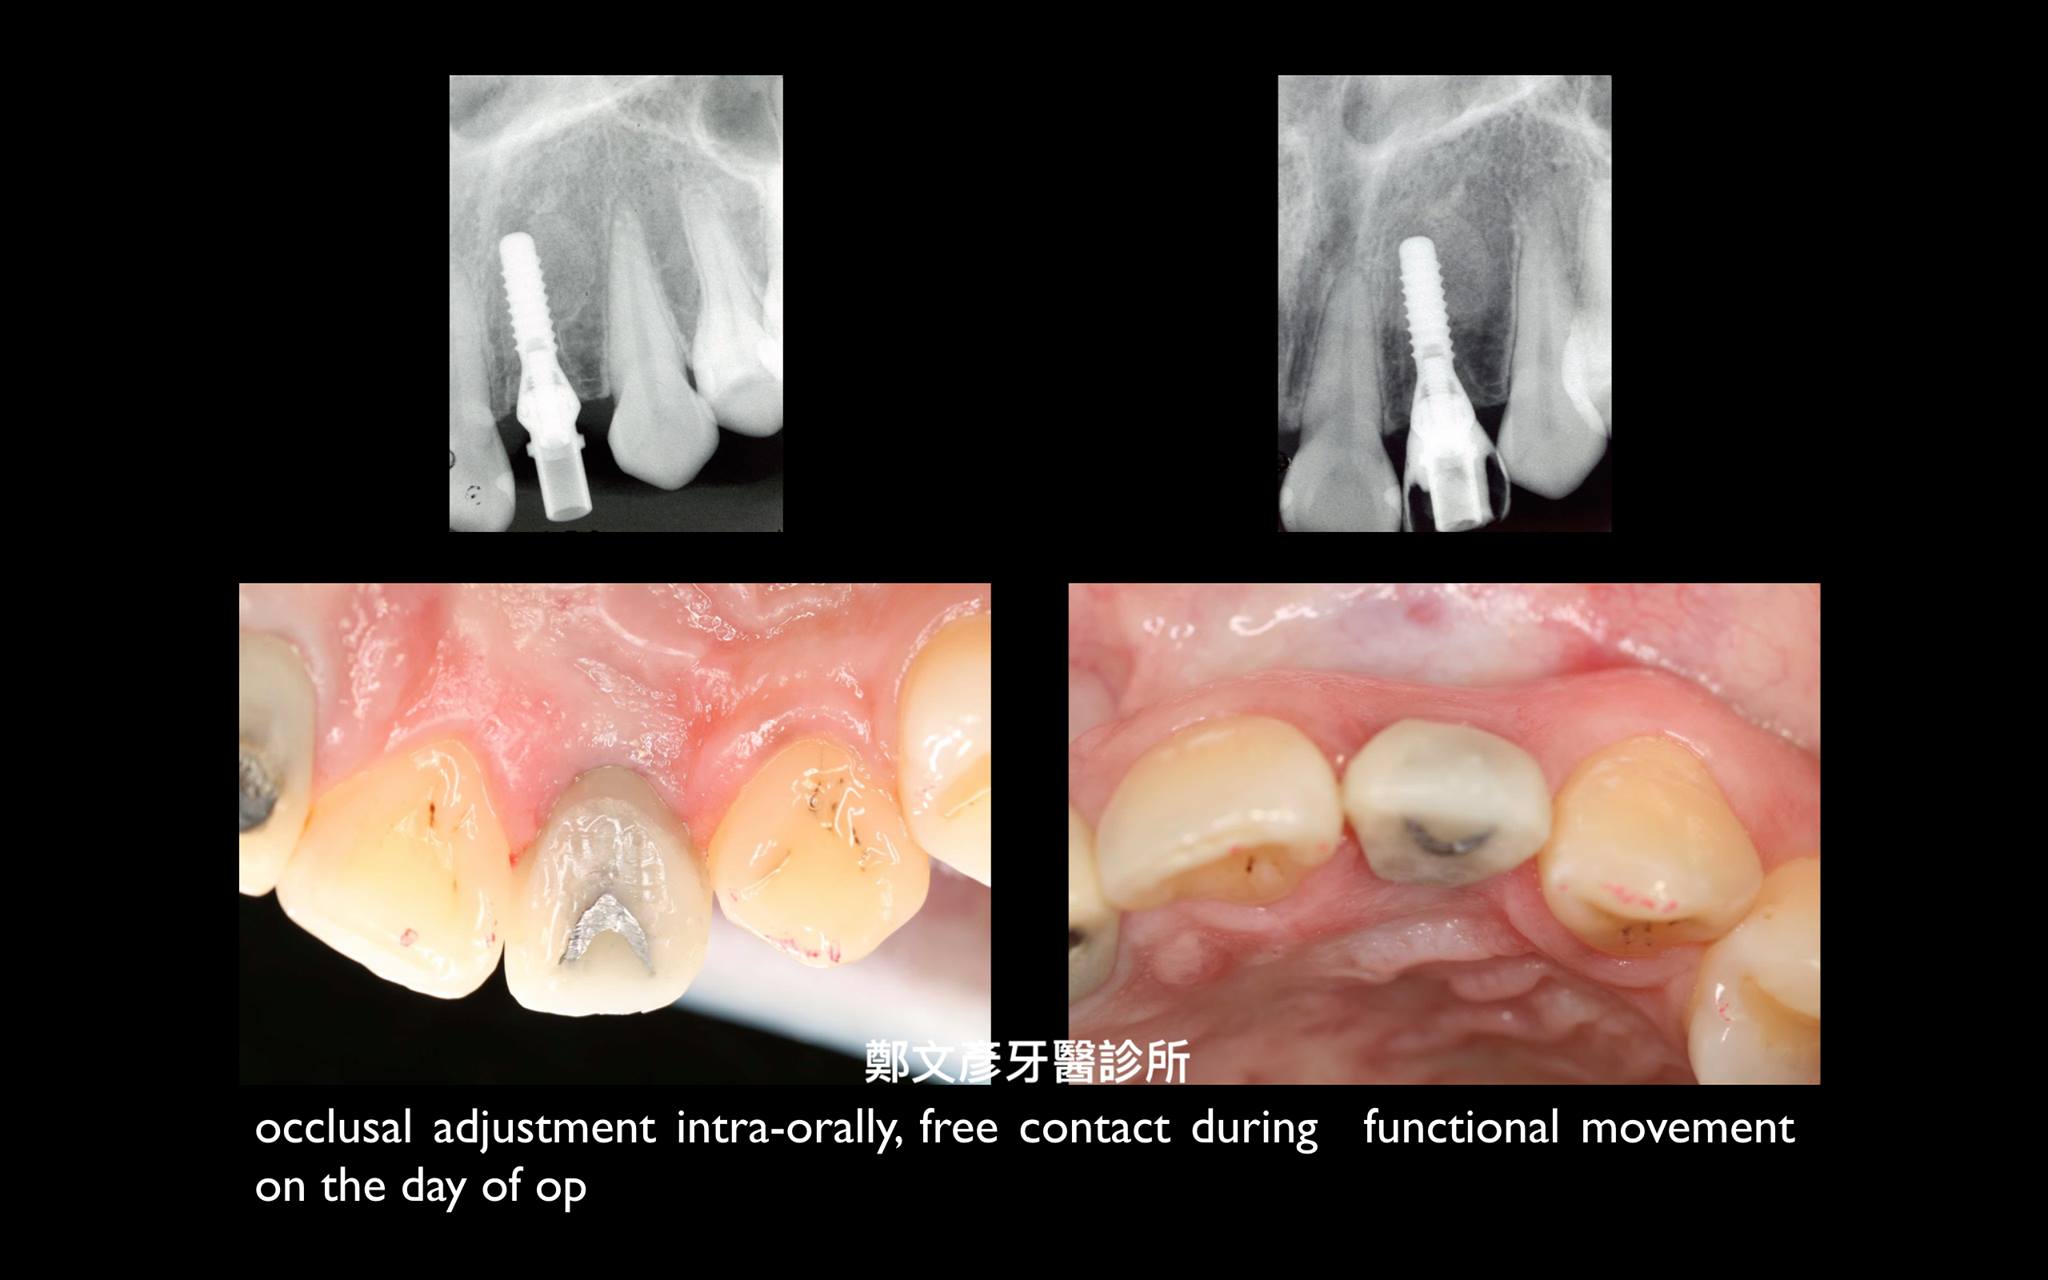

前牙植牙美學及軟組織轉移

植牙美學